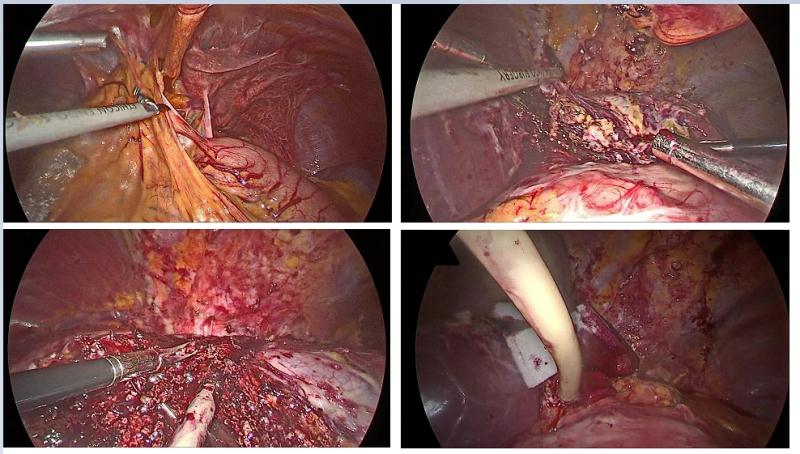

肝内胆管结石是我国常见而难治的胆道疾病,术后结石残留率在20%-40%之间。手术难度大,治疗比较棘手。近期,我院普外三科延学军团队收治一复杂肝内胆管结石病人,该病人以“间断右上腹部胀痛不适10年余”为主诉入院。该病人长期一直按胃病治疗,近2年来,症状加重,才引起重视。辗转多家医院,均因病情复杂,建议转院治疗。(该病人入院后相关检查结果如下:)

相关链接:我院普外三科在微创治疗肝内外结石方面,技术力量雄厚,尤其擅长复杂胆道肝脏胰腺手术的处理。开展业务醉早、新技术新业务引进醉早,临床经验丰富,在豫西南有较高的口碑。欢迎咨询、欢迎就诊!